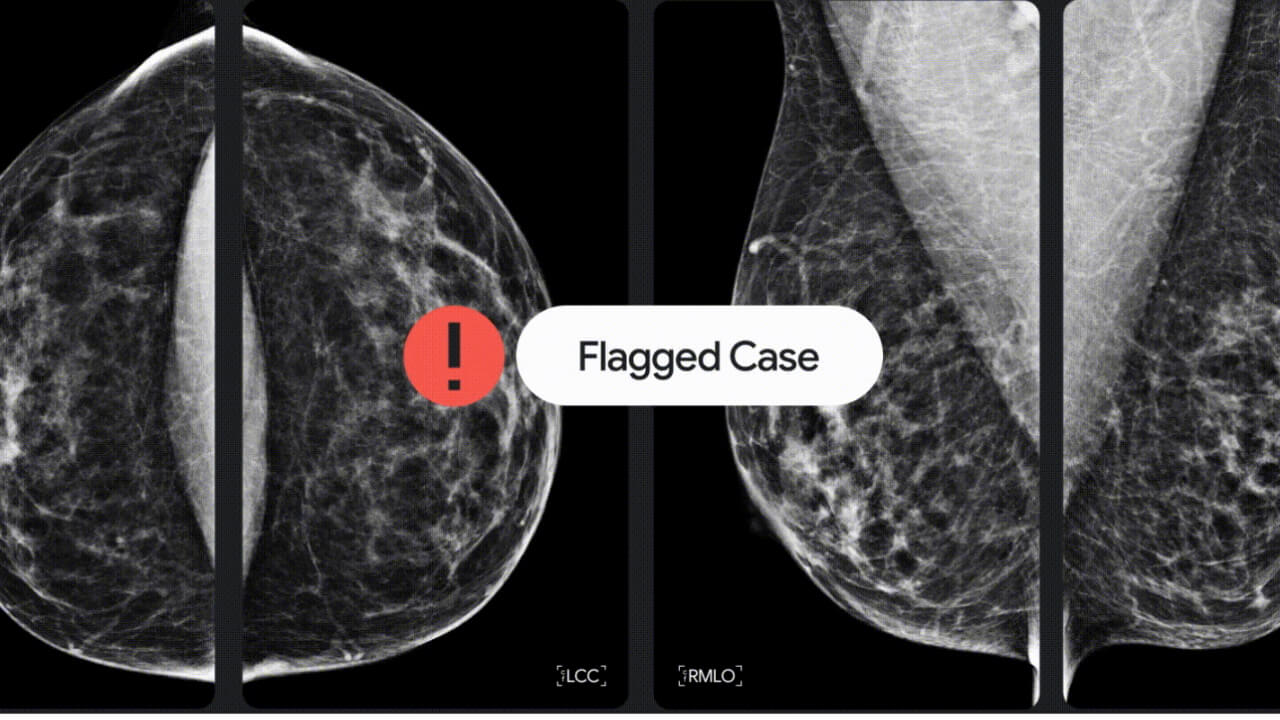

Google は 2022 年 11 月 28 日(月)、乳がん検出技術向上に向けた米医療機器メーカー iCAD Inc. との、初の商業提携を発表しました。

Google と iCAD の提携では、乳がん検診利用可能性拡大などを目的として、Google 健康情報サービス「Google Health」の精度向上のための開発が行われます。また逆に、乳がん検診に関連するサービスを十分に受けていない地域に対して、Google Cloud を介した AI ベースツールの提供も拡大します。

つまり今後、「Google Health」にアクセスできるデバイスやサービスが、ユーザーの乳がん危険性を察知したり、乳がんなどの健康データをさらなる乳がん検出技術向上のために役立てられるということ。昨今 Android や Google ウェアラブルデバイスは、ユーザーの健康管理に役立つ呼吸数や心拍数、最大酸素摂取量(VO2 Max)などを検出できるようになっていますが、今後は Android や Google ウェアラブルデバイスが乳がんの早期発見に役立つ日が来るのかもしれません。